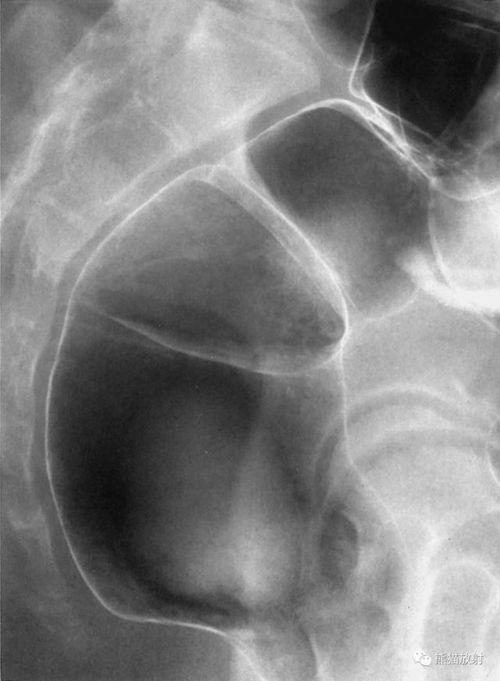

4. 肾脏检查:肾脏造影可以显示肾脏的形态、大小、血管分布等,有助于诊断肾脏疾病。